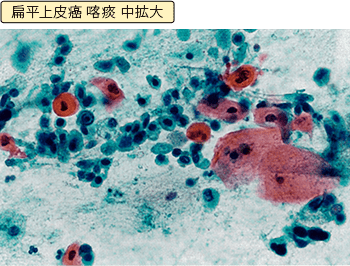

喀痰細胞診とは、痰を採取して、痰に混じっているがん細胞があるかどうかを顕微鏡で観察する方法です。喫煙者に多いとされる、気管支の太い部分にできる扁平上皮癌は、この検査で見つかる可能性があります。喀痰細胞診の検査対象となるのは、50歳以上で、喫煙指数(1日の喫煙本数×喫煙年数)が600以上の人と定められています。現在たばこを吸っている人だけでなく、過去にたばこを吸っていた人も対象となります。喀痰細胞診は、必ずレントゲン検査と一緒に行われます。

痰に混じったがん細胞を見つけ出す:喀痰細胞診

喀痰細胞診

出典:「臨床・病理 肺癌取扱い規約」2017年1月改訂

第8版 金原出版株式会社 日本肺癌学会 編

喀痰とは吐き出した痰のことです。肺の組織から剥がれ落ちて痰に混じったがん細胞を検出する検査です。人間の目で喀痰中のがん細胞の有無をチェックします。検査は専門のスクリーナーという技師が行います。

検査の手順は、できるだけ早朝の喀痰を容器に入れ、乾かないようにして提出するだけです。患者さんにとって苦痛のない簡単な検査ですが、肺がんがあれば必ず痰にがん細胞が混じっているとは限らず、喀痰細胞診の結果が正常であったからといって肺がんがないという証拠にはなりません。

そのため喀痰細胞診は何回か繰り返し行うことで、がんがあった場合の診断精度が高まるとされており、通常3回は行って喀痰中のがん細胞の有無を調べることになっています。

医療施設から遠方にお住まいの人、忙しい人などに自宅で3日間痰をためてもらう方法もありますが、どうしても細胞が変性してしまうため、少し見にくい標本になってしまうようです。

細胞診検査では、検体(この場合痰のことです)をスライドグラスの上で伸ばしてアルコールで固定し、染色して顕微鏡で細胞を観察します。がん細胞があると疑われる場合には、スクリーナーとは別に医師が確認するという手順を踏みますので、結果が出るまでは数日かかります。